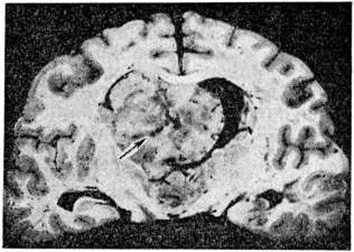

Макроскопически Олигодендроглиома имеет вид узла, чаще нечётко отграниченного от окружающего мозгового вещества (рисунок 1). Ткань опухоли однородного сероватого, серовато-розового, реже красноватого цвета, консистенция либо соответствует мозговому веществу, либо студенистая с наличием мелких кист.

Рис. 1.

Макропрепарат фронтального среза больших полушарий головного мозга с узловой олигодендроглиомой (указана стрелкой) паравентрикулярной области.